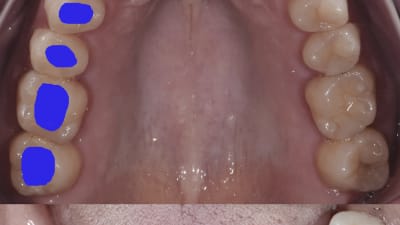

Case Reports Periodontics Repair of Lingual Gingival Fenestrations Through the Use of a Subepithelial Connective Tissue Graft By Elena Sanz-Miralles, DDS, Gary Greenstein, DDS, Joshua Shayefar, DMD, Robert N. Eskow, DMD September 01, 2020 11 min read